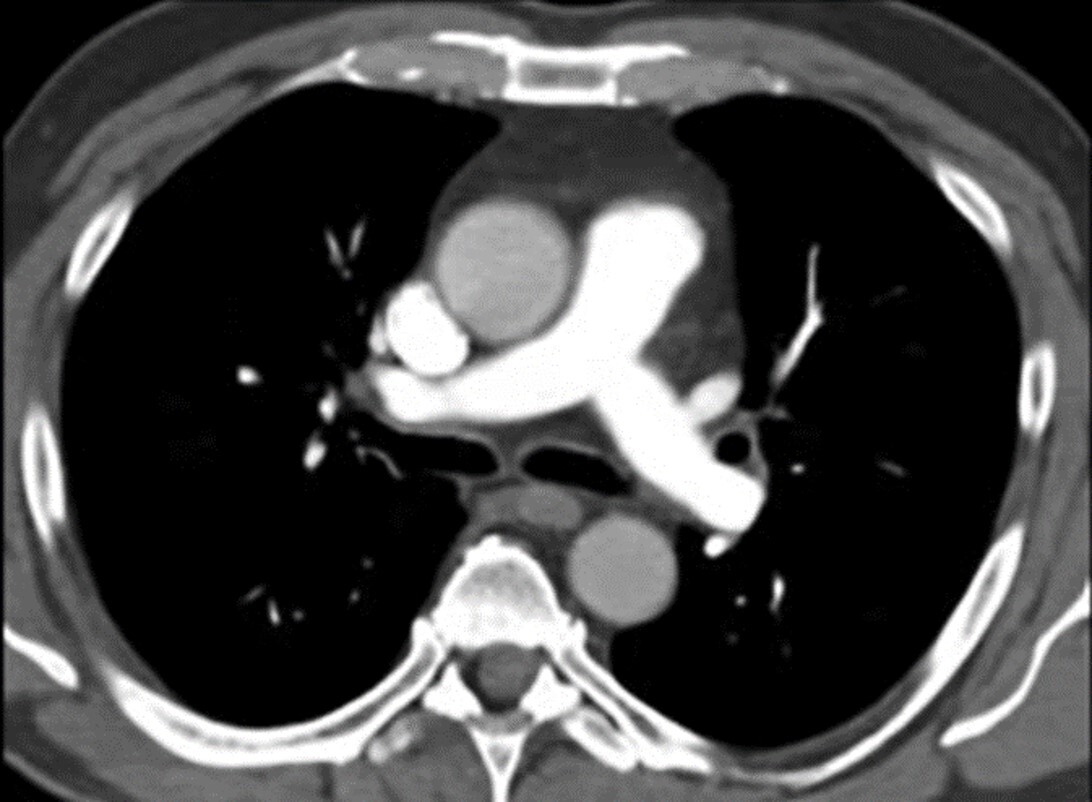

Q

Is this study positive for PE?

a. Yes

b. No

A

Yes